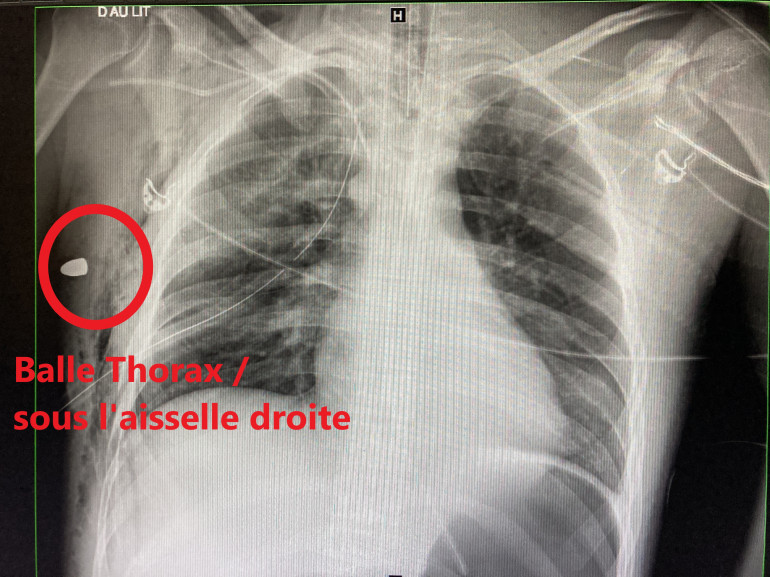

Radio blessé par balle - aisselle

Extraire une "bastos" est rarement la priorité. Des radiologues opérationnels obstruent les vaisseaux qui saignent, freinent les lésions dans les organes vitaux. Plus de 9 patients sur 10 dans ce service survivent aux premières heures.